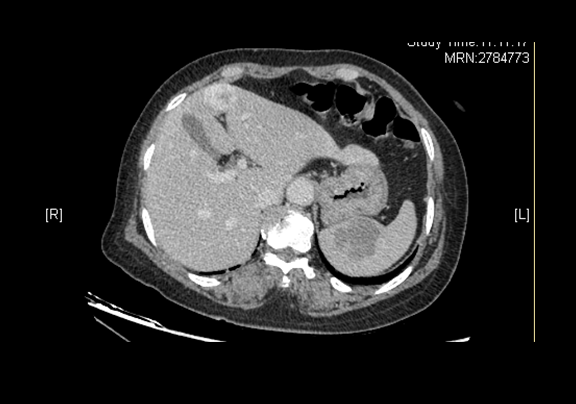

术前CT检查:

静脉期

辅助检查:2015-12-07

全腹CT 肝左叶内略低密度灶,脾脏内略低密度灶

肝胆胰脾彩色多普勒超声检查 脾脏实性占位

上腹部CT平扫 “脾脏术后”改变,请结合临床综合评价,肝脏血管瘤可能性大,请综合临床及其它检查进一步诊断